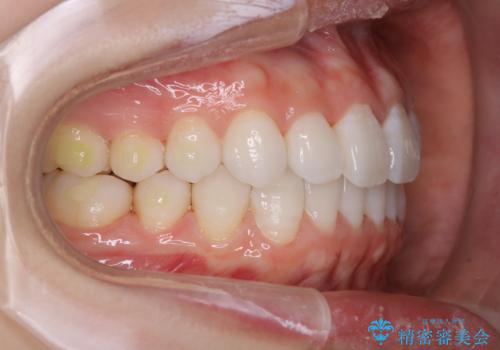

- インビザライン(マウスピース矯正)の治療中にステインが気になり、クリーニング希望とのことでした。

アタッチメントの周囲などに、ステインの付着や、プラークがみられたためPMTC(自費クリーニング)30分コースを行いました。

自費クリーニング(pmtc)30分コース¥5000+tax